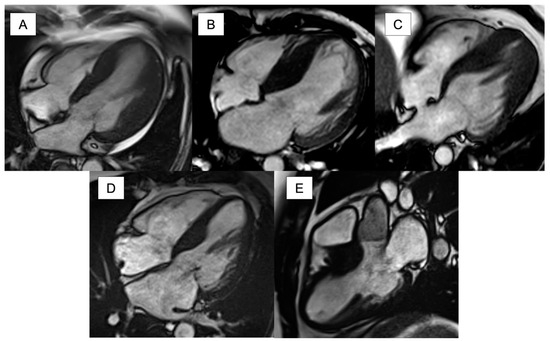

5.1. Anatomy/Morphology and Function

- Moon, J.C.C.; Fisher, N.G.; McKenna, W.J.; Pennell, D.J. Detection of apical hypertrophic cardiomyopathy by cardiovascular magnetic resonance in patients with non-diagnostic echocardiography. Heart 2004, 90, 645–649. [Google Scholar] [CrossRef]

- Maron, M.S.; Finley, J.J.; Udelson, J.E.; Bos, J.M.; Ackerman, M.J.; Hauser, T.H.; Manning, W.J.; Haas, T.S.; Lesser, J.R.; Maron, B.J.; et al. Prevalence, Clinical Significance, and Natural History of Left Ventricular Apical Aneurysms in Hypertrophic Cardiomyopathy. Circulation 2008, 118, 1541–1549. [Google Scholar] [CrossRef]

- Maron, M.S.; Rowin, E.J.; Lin, D.; Appelbaum, E.; Gibson, C.M.; Chan, R.H.; Lesser, J.R.; Lindberg, J.; Haas, T.S.; Udelson, J.E.; et al. Prevalence and Clinical Profile of Myocardial Crypts in Hypertrophic Cardiomyopathy. Circ. Cardiovasc. Imaging 2012, 5, 441–447. [Google Scholar] [CrossRef]

- Rowin, E.J.; Maron, B.J.; Haas, T.S.; Garberich, R.F.; Wang, W.; Link, M.S.; Maron, M.S. Hypertrophic cardiomyopathy with left ventricular apical aneurysm: Implications for risk stratification and management. J. Am. Coll. Cardiol. 2017, 69, 761–773. [Google Scholar] [CrossRef]

- Maron, M.S.; Rowin, E.J.; Maron, B.J. How to Image Hypertrophic Cardiomyopathy. Circ. Cardiovasc. Imaging 2017, 10, e005372. [Google Scholar] [CrossRef]

- Yang, K.; Song, Y.-Y.; Chen, X.-Y.; Wang, J.-X.; Li, L.; Yin, G.; Zheng, Y.-C.; Wei, M.-D.; Lu, M.-J.; Zhao, S.-H. Apical hypertrophic cardiomyopathy with left ventricular apical aneurysm: Prevalence, cardiac magnetic resonance characteristics, and prognosis. Eur. Heart J.—Cardiovasc. Imaging 2020, 21, 1341–1350. [Google Scholar] [CrossRef] [PubMed]